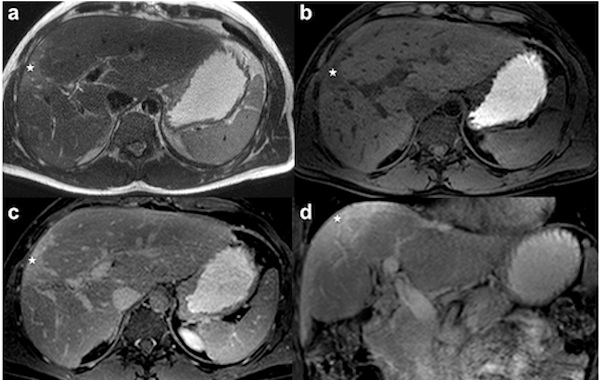

-gan-vai-tr%C3%B2-%C6%B0u-nh%C6%B0%E1%BB%A3c-%C4%91i%E1%BB%83m-quy-tr%C3%ACnh/mri-phat-hien-duoc-cac-ton-thuong-nho-o-gan.jpg)

MRI phát hiện được các tổn thương nhỏ ở gan

Mặc dù siêu âm và CT là hai kỹ thuật chẩn đoán hình ảnh được dùng phổ biến để chẩn đoán bệnh gan, nhưng ngày này MRI ngày càng được chứng minh nhạy hơn để phát hiện các di căn gan nhỏ và tổn thương gan khu trú nhỏ.

Điều này đến từ khả năng chẩn đoán tốt các mô mềm của MRI, cho phép phát hiện và mô tả các tổn thương nhỏ. Chụp cộng hưởng từ sử dụng thuốc tương phản còn cải thiện tốt hơn nữa khả năng mô tả đặc điểm tổn thương ở gan.

MRI còn là phương pháp chẩn đoán trước phẫu thuật gan để có được các thông tin về số lượng, kích thước, vị trí để xác định khả năng phẫu thuật và lên kế hoạch phẫu thuật.